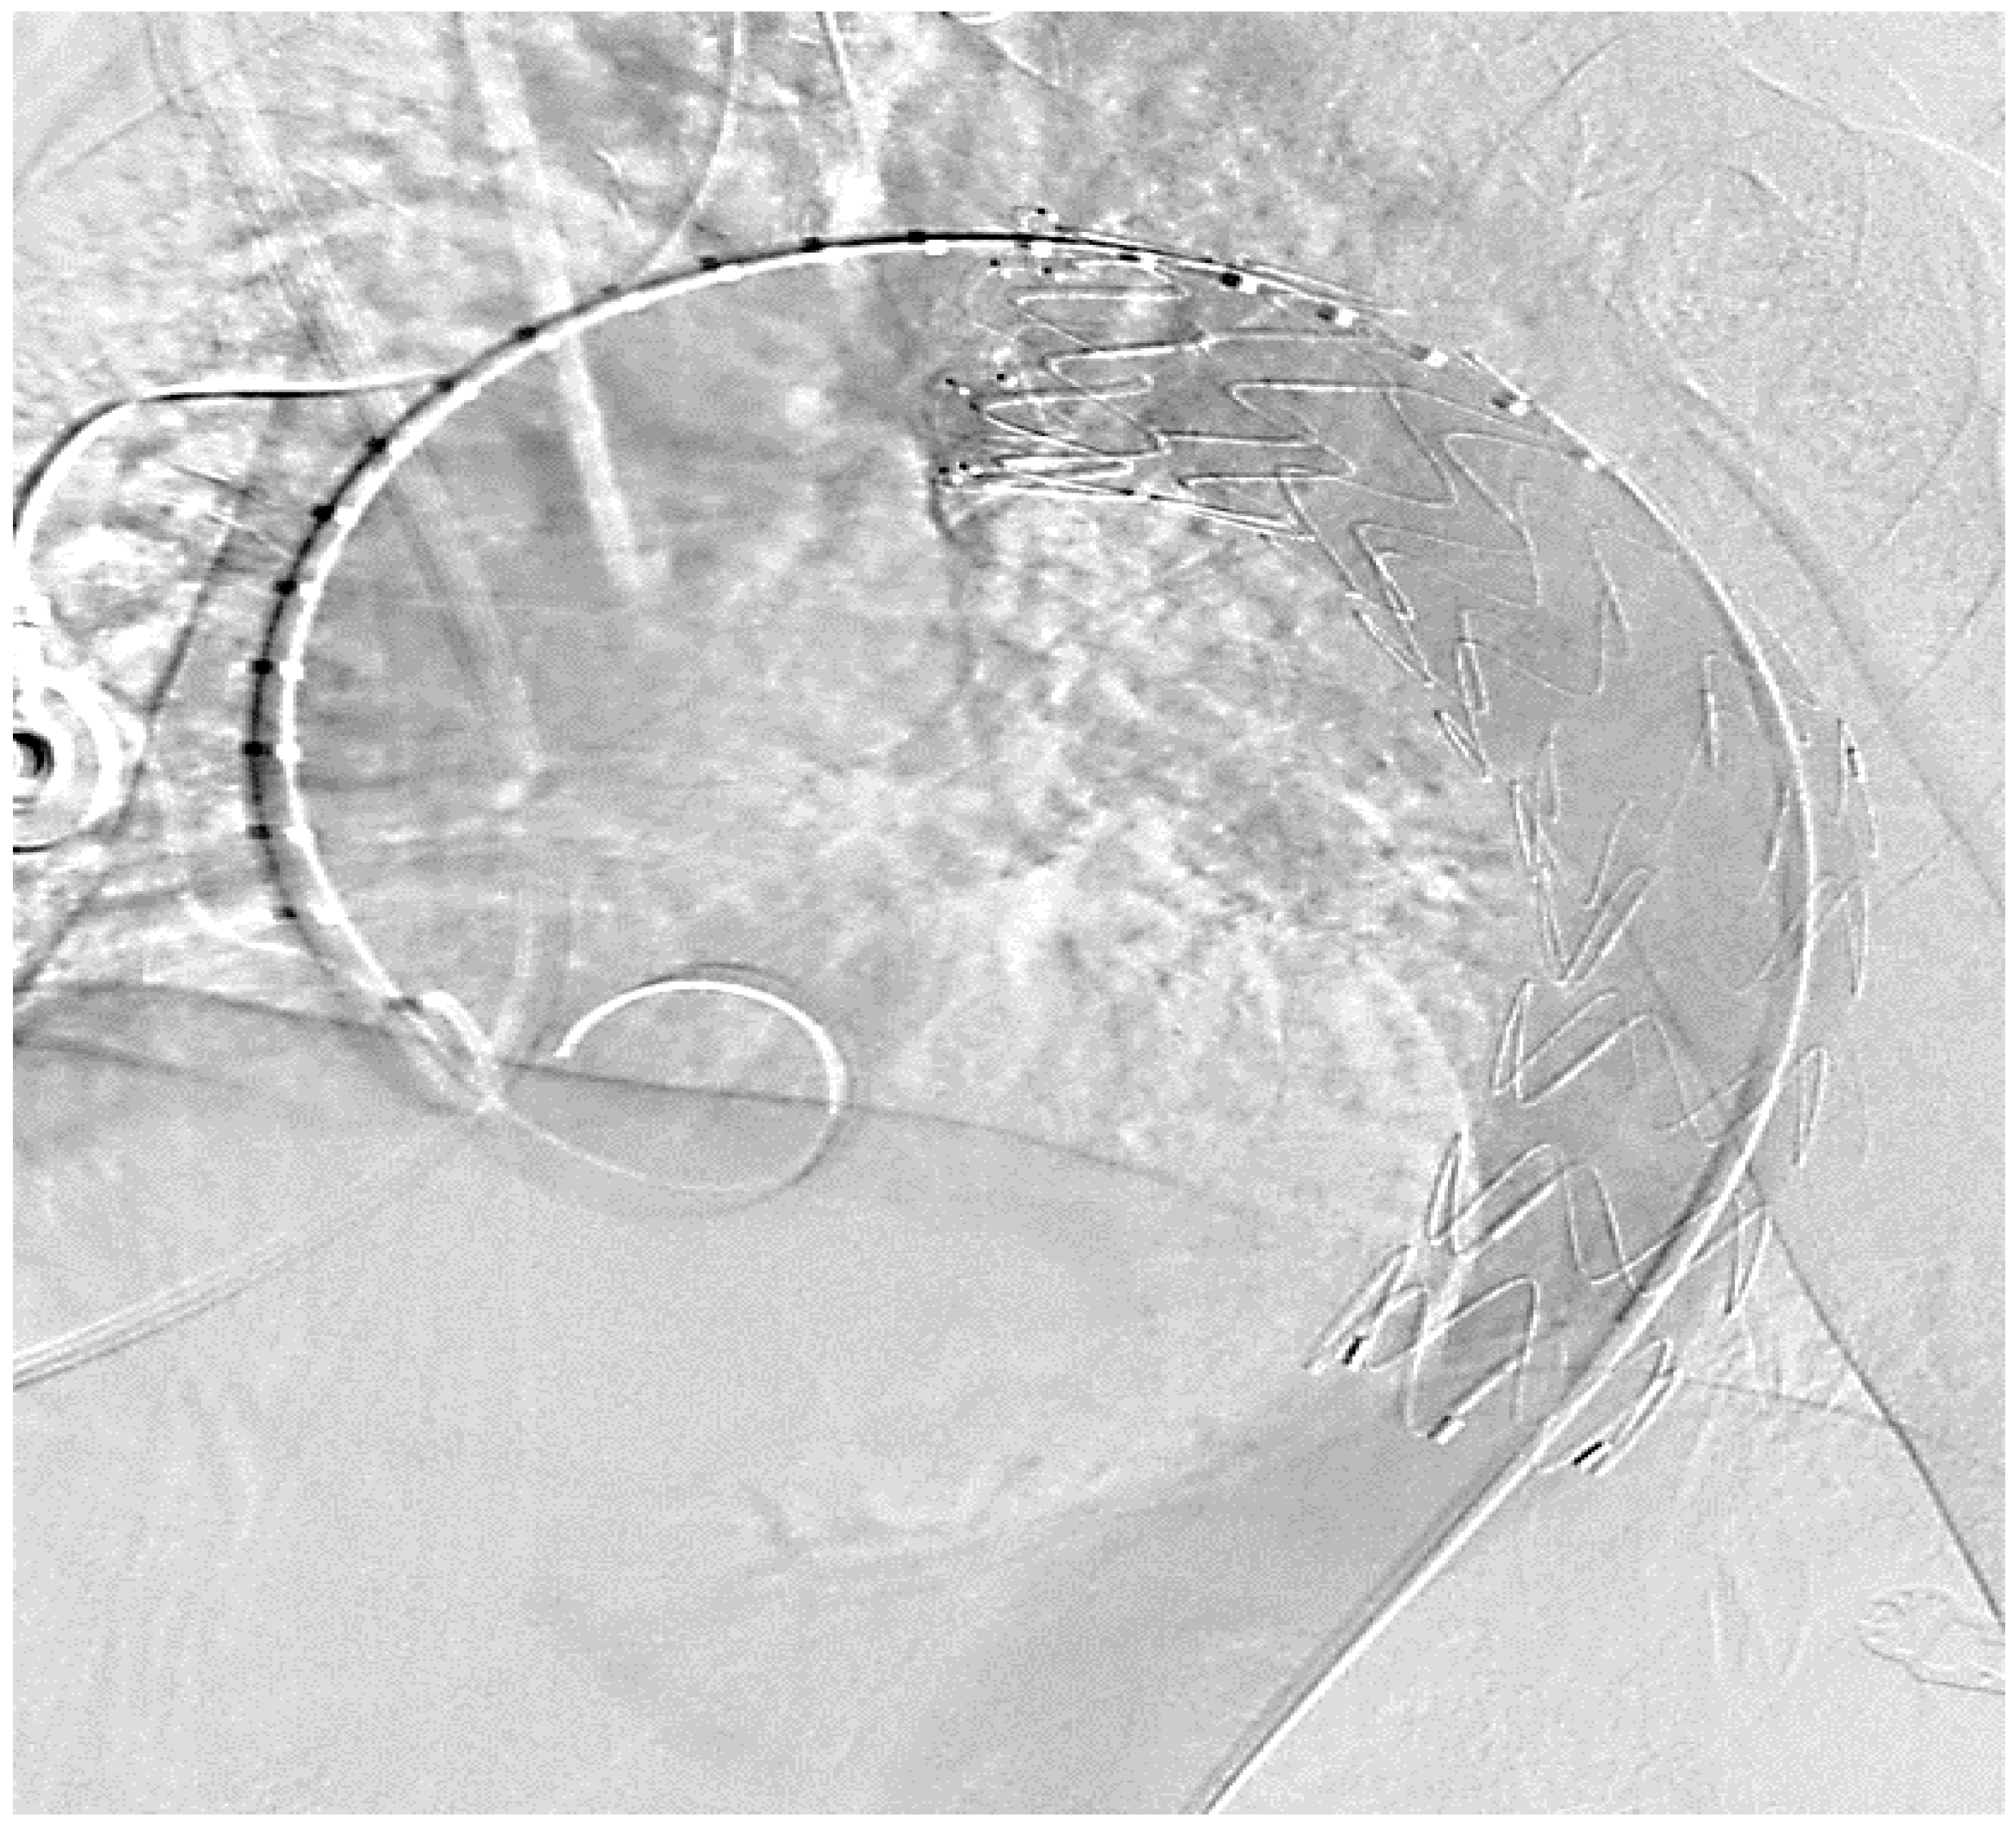

4.2. Aortic Stent Implantation